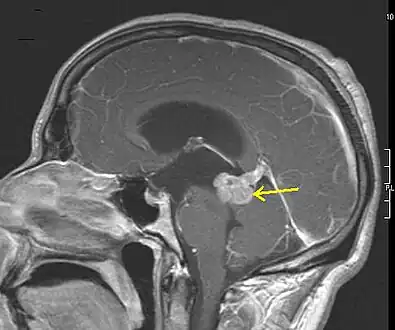

An X-ray computed tomography (CT) or magnetic resonance imaging (MRI) scan is necessary to characterize the extent of these tumors (size, location, consistency). CT will usually show distortion of third and lateral ventricles with displacement of anterior and middle cerebral arteries. Histologic analysis is necessary for grading diagnosis.

In the first stage of diagnosis the doctor will take a history of symptoms and perform a basic neurological exam, including an eye exam and tests of vision, balance, coordination, and mental status. The doctor will then require a CT scan and MRI of the patient's brain. During a CT scan, X-rays of the patient's brain are taken from many different directions. These are then combined by a computer, producing a cross-sectional image of the brain. For an MRI, the patient relaxes in a tunnel-like instrument while the brain is subjected to changes of magnetic field. An image is produced based on the behavior of the brain's water molecules in response to the magnetic fields. A special dye may be injected into a vein before these scans to provide contrast and make tumors easier to identify.

If a tumor is found, a neurosurgeon must perform a biopsy on it. This simply involves the removal of a small amount of tumor tissue, which is then sent to a neuropathologist for examination and grading. The biopsy may take place before surgical removal of the tumor or the sample may be taken during surgery. Grading of the tumor sample is a method of classification that helps the doctor to determine the severity of the astrocytoma and to decide on the best treatment options. The neuropathologist grades the tumor by looking for atypical cells, the growth of new blood vessels, and for indicators of cell division called mitotic figures.